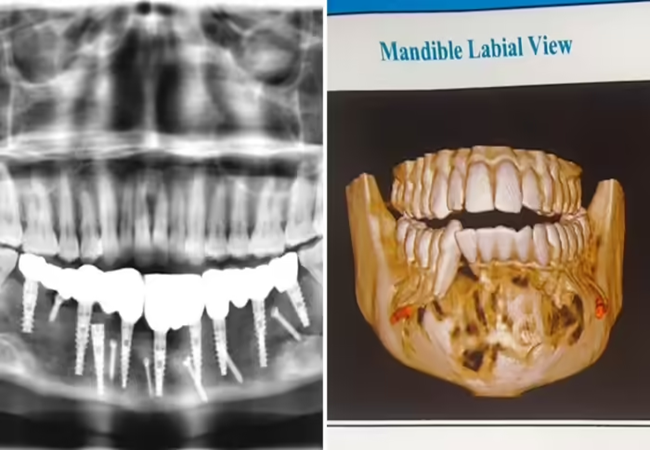

Jaw tumour : मुंह में सूजन-पस लेकर AIIMS पहुंची 24 साल लड़की, रिपोर्ट देख डॉक्टर के उड़े होश

अगर किसी के मुंह दर्द होता है तो वो ज्यादा से ज्यादा यही सोच सकता है कि दांतों में कीड़ा लगा होगा। लेकिन 24 साल कि इस लड़की के लिए ये प्रॉबलम किसी भयानक  दास्तां से कम नहीं है।  युवती को कई दिनों से मुंह में सूजन और बार बार